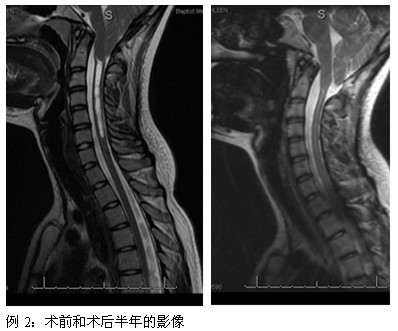

本病的发病机理尚未完全阐明,目前比较为大家所接受的观点基本均认为脑脊液动力异常是该病继发脊髓空洞的动因。因此,改变异常的解剖结构、恢复脑脊液的正常动力学状态已成为外科干预的主要方式。事实证明,外科治疗可以使大多数空洞的状况得以改善,已经形成的空洞可以停止发展,甚至消失。

(1)颅颈交界区减压手术:通过手术解除环枕区骨性结构对小脑、脊髓等结构的压迫,从而恢复正常的脑脊液动力学循环通路,从病因的角度对该病进行治疗。